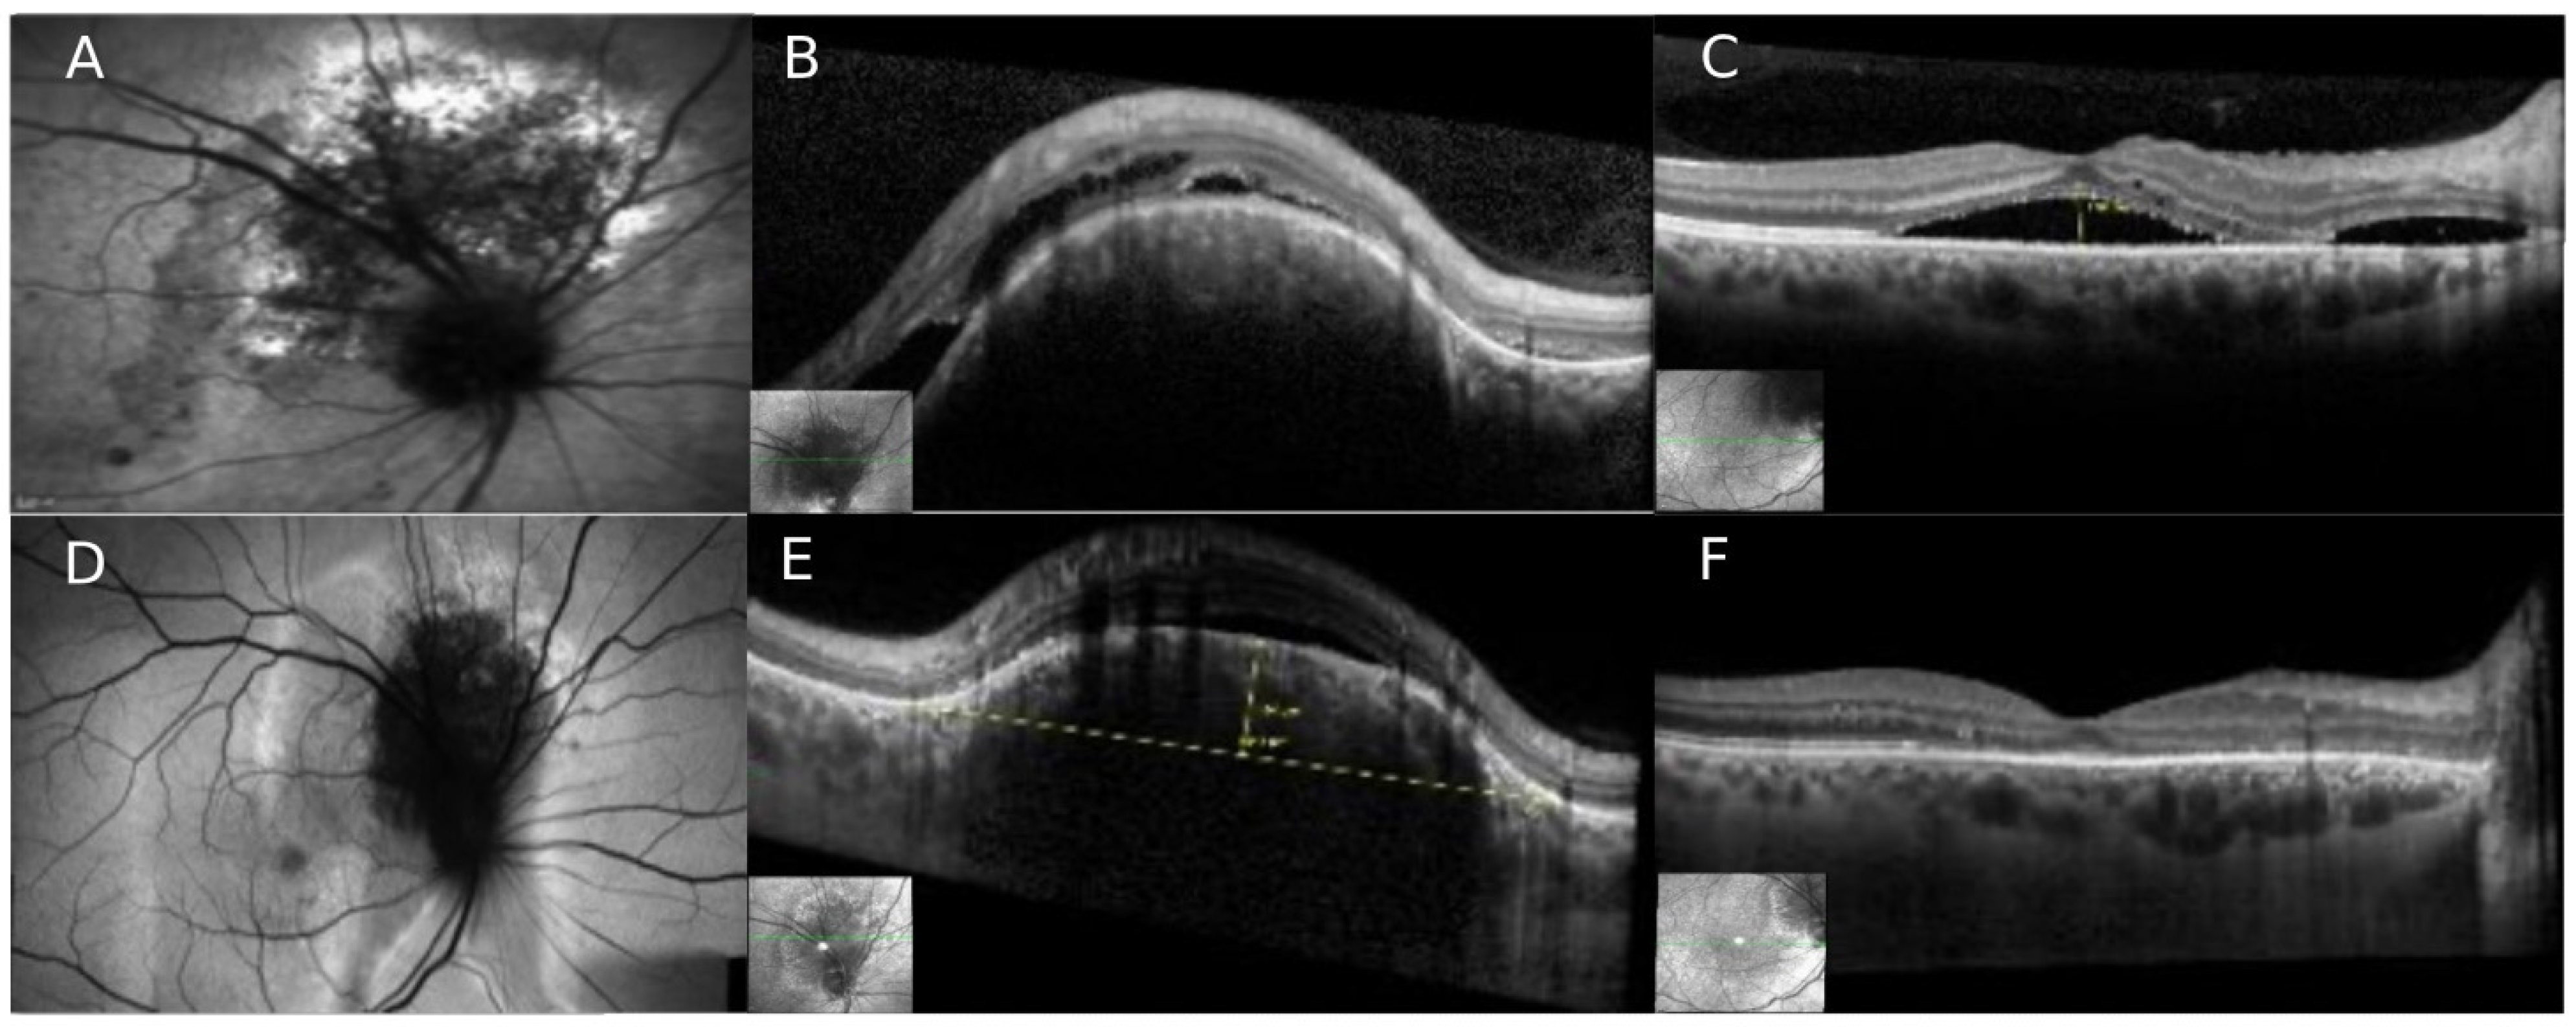

4. Case Number 3